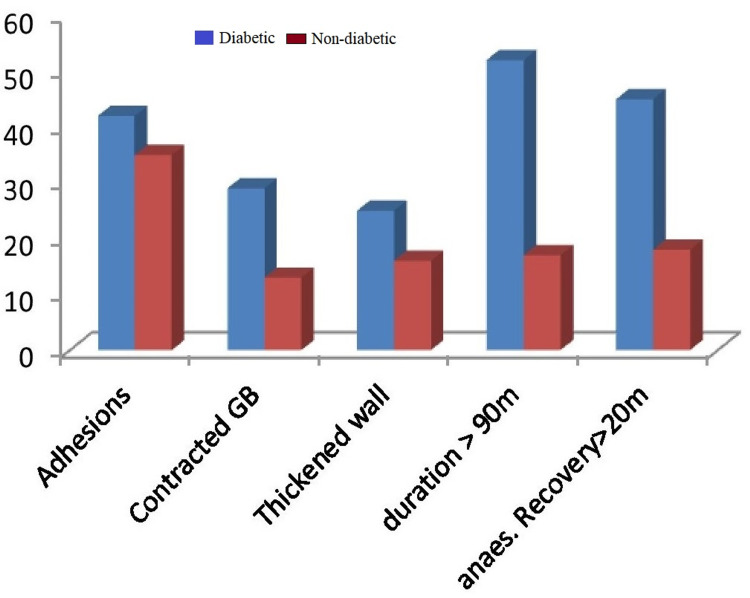

Pericholecystic adhesions (Figure 1), contracted gallbladder (Figure 2), gallbladder wall thickening, and frozen Calot’s triangle were observed significantly more among diabetic patients in comparison with nondiabetic patients. However, impaction of stone in Hartman’s pouch was present in six patients (8%) in the diabetic group in comparison with four patients (5.3%) in the nondiabetic group (Table 1).

| Duration of surgery (more than 90 minutes) | 69.30 | 36 | 0.00001 |

| Recovery from anesthesia (more than 20 minutes) | 60 | 24 | 0.0001 |

Subtotal cholecystectomy was done in four patients (5.3%) in the diabetic group and two patients (2.6%) in the nondiabetic group. The reason for subtotal cholecystectomy was frozen Calot’s anatomy in both groups of patients. Conversion to open procedure was done in 4% of diabetic patients due to dense adhesions, altered anatomy, and inability to proceed to laparoscopy. The mean duration of surgery was taken as 90 minutes, and it exceeded in 52 diabetic patients (69.3%) and 27 nondiabetic patients (36%). A drain was given in 14 patients (18.6%) in the diabetic group and nine patients (12%) in the nondiabetic group. A tube drain was inserted in all patients with subtotal cholecystectomy and open conversion. Recovery from anesthesia was more than 20 minutes in 45 patients (60%) in the diabetic group and 18 patients (24%) in the nondiabetic, which was statistically significant. The reason for delayed anesthesia recovery was various intraoperative and metabolic factors in diabetes. Intraoperative injury was not reported in CBD or surrounding organs (Figure 3).

The duration of surgery of diabetic patients was significantly higher than nondiabetic patients because of more adverse intraoperative findings. Intraoperative findings such as pericholecystic adhesions, contracted gallbladder, thickened wall, impacted stone in Hartman’s pouch, and frozen Calot’s anatomy are more often seen in diabetics. All these factors contribute to operative difficulty, increased time, complications, and also open conversion. This was reflected in our study populations, except for frozen Calot’s anatomy, similar in both groups. Different pain sensations and less sensitivity in diabetic neuropathy also result in a delayed diagnosis [ref. 13]. This leads to repeated silent attacks of cholecystitis.